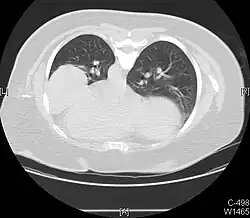

Hemothorax

Massive right sided pleural effusion later confirmed to be a hemothorax

Hemothorax, or accumulation of blood in the pleural space, can result from trauma or surgical procedures in the chest. This accumulation of blood can grow large enough to compress the lung and push away other structures in the chest, thus causing a mediastinal shift.[6] On a chest x-ray, a hemothorax can appear similarly to a pleural effusion with blunting of the pleural recess and white out of normal lung zones.[7] In the setting of traumatic chest injury, rib fractures are also commonly observed on x-ray.[8]